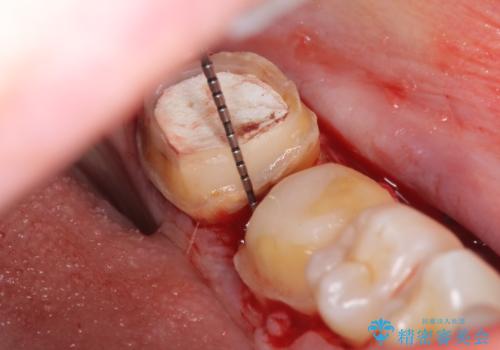

また左下6は遠心にあった歯茎より深い虫歯(縁下カリエス)の問題を解決するため、歯茎を下げる歯周外科手術を行いました。

歯周外科手術終了後、歯茎の回復を待ち左下6、7ともにオールセラミッククラウン(スタンダード)による補綴を行いました。